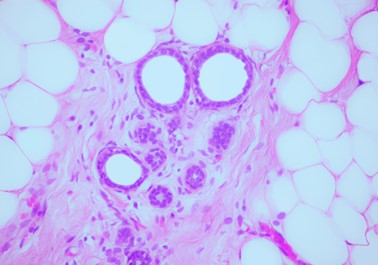

W procesie nowotworzenia ujawnia się fundamentalny paradoks – przenikanie się życia i śmierci. Nowotwórczość komórek wyraża ich dążenie życia i namnażania. Jednak to właśnie ich chaotyczny wzrost prowadzi ostatecznie do destrukcji. Z drugiej strony, śmierć komórek nowotworowych otwiera drogę do życia. Ich eliminacja przez mechanizmy obronne ciała lub interwencje terapeutyczne przywraca równowagę i umożliwia kontynuację życia. Tak oto w procesie nowotworzenia śmierć i życie wzajemnie się warunkują – tworząc nieustanny ruch przeciwieństw rozgrywający się w ciele. Zdjęcie mikroskopowe autorstwa Małgorzaty Lisowskiej przedstawiające jej własne komórki nowotworowe z biopsji, tkankę po szesnastu chemioterapiach oraz zdrowe komórki piersi po mastektomii.

Fotografka mikroskopowa. Zwyciężczyni prestiżowego konkursu Nikon Small World 2023 zdjęciem własnych komórek nowotworowych – pierwszy powrót Polski na podium po 31 latach. Autorka wystawy "Historia zapisana w ciele w trzech aktach", prezentowanej m.in. w Narodowym Funduszu Zdrowia.